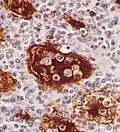

Emperipolesis in Rosai-Dorfman disease highlighted by S-100 staining.

Emperipolesis in Rosai-Dorfman disease highlighted by S-100 staining. -